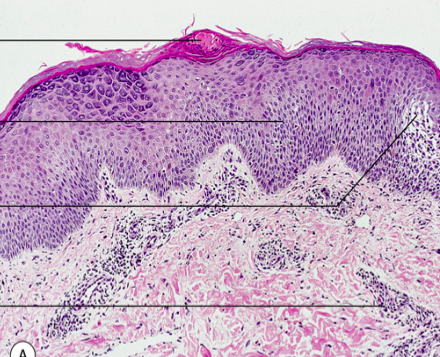

Vad är detta?

Lichen planus

Orsak och hereditet: Okänd etiologi, ingen känd hereditet

Kliniska kännetecken: Kliande, platta rödvioletta papler. Köbnerfenomen.

Lokalisation: Hanleder och buccalslemhinna är vanligast.

Histologi: Hyperortokeratos, hypergranulos, sågtandad acantos